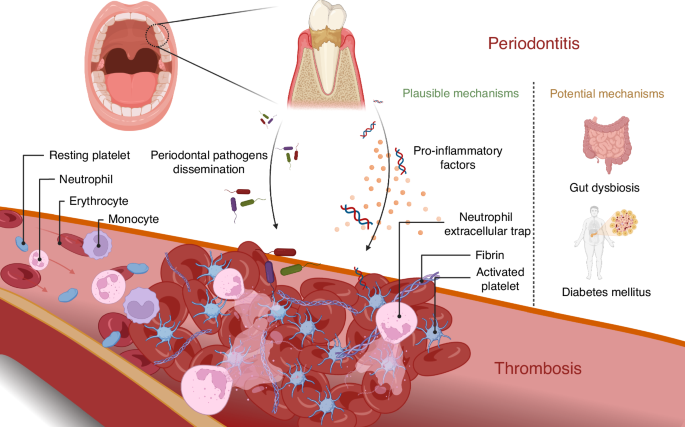

Tandköttet börjar blöda lite när du borstar tänderna. Kanske känns det svullet. Du tänker att du borde bli bättre på tandtråd som tandläkaren har sagt, men annars känns det inte som något stort problem.